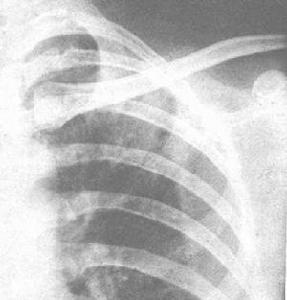

其他輔助檢查:X線表現:大葉實變、小葉浸潤、膿腫形成。大葉實變多位於右上葉,由於炎性滲出物量多,黏稠且重,故葉間裂呈弧形下墜。炎症浸潤中見膿腫,胸腔積液,少數呈支氣管肺炎。

⑤X線胸片示肺段或大葉性緻密實變陰影,其邊緣往往膨脹凸出。可迅速發展到鄰近肺段,以上葉後段及下葉前段較多見;

⑥常見併發症為肺膿腫,可呈多房性蜂窩狀,日後形成纖維性變;其次為膿胸及胸膜肥厚。治療尚缺乏有效抗菌藥物。